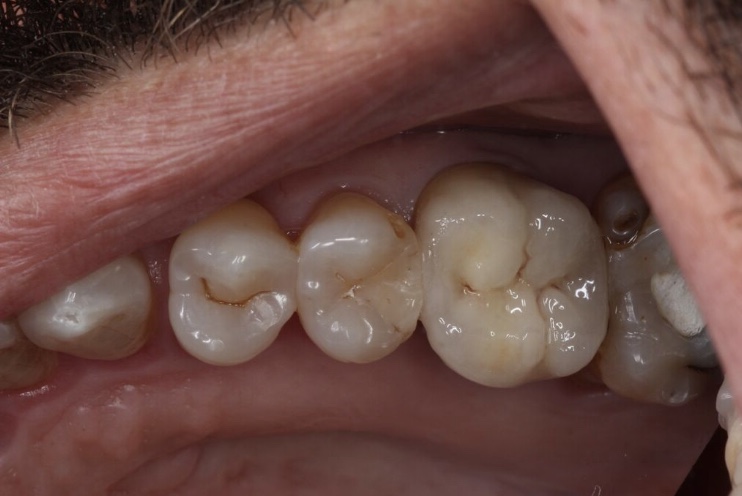

E-Max

L’E.max®, 100% céramique, est à base de disilicate de lithium, reconnu pour sa haute résistance à la flexion (500 Mpa).

Elle est donc une alternative esthétique aux restaurations céramo-métalliques, conservant, ensemble, éclat et durabilité.

Couronne, bridge de 3 éléments, inlay, onlay, facette